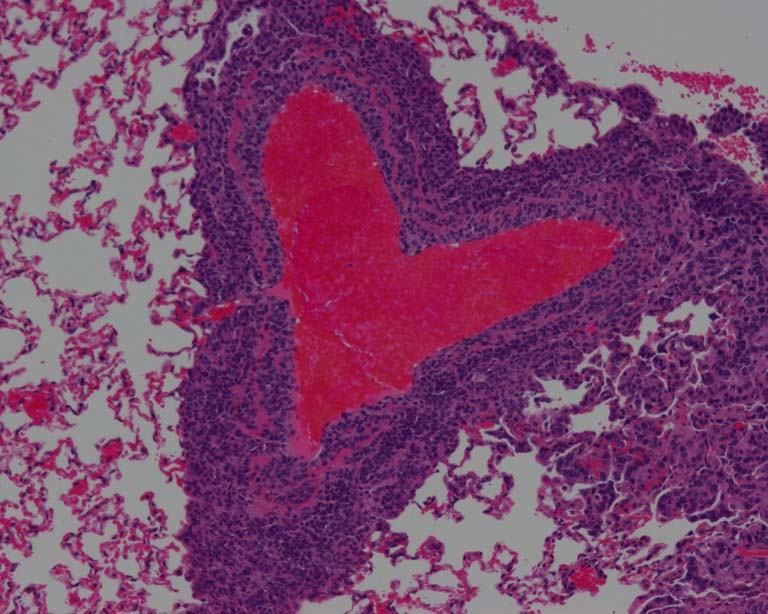

This image shows a metastatic tumor growing around a blood vessel in lung tissue. The red-stained cells are red blood cells, and the purple-stained nuclei surrounding them belong to tumor cells and some immune cells, which have infiltrated the tumor.

This slide is part of a series of histological slides that capture tumor cells that have metastasized to the lungs. This is part of an experiment to investigate the molecular changes that drive the process of metastasis. We initially noticed this particular tumor because of its interesting shape, and we think this slide serves as a great example to highlight the extravasation step of metastasis, which is when tumor cells traveling in the blood vessels from the primary tumor leave the circulation and begin to colonize the surrounding tissue.